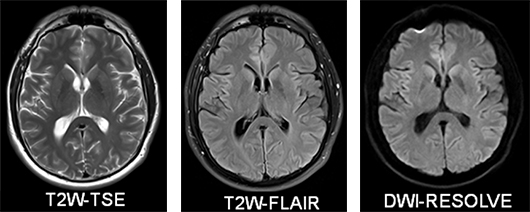

<SIEMENS社製MAGNETOM skyra3.0テスラ(T)MRIのご紹介>

3.0テスラの強い磁場で検査することにより、より強い信号が得られるため情報量が多く、より高分解能(高画質)な画像、より短時間撮影が可能となりました。

第4世代Timテクノロジー(Tim4G)搭載

MAGNETOM Skyraは、最も進化した世代のコイルテクノロジー:Tim4Gを搭載しています。それにより、広範囲をカバーするひとつの高密度コイルとして、局所を対象にした超高分解能撮像や、全身に点在する腫瘍のスクリーニング、病因を特定するための全身検査が可能です。

多彩な専用コイルで高画質

頭部や脊椎、乳房専用コイル、肩関節専用、膝関節専用、手指関節専用など撮像部位に応じた多彩なコイルを用意しています。

[造影両乳房撮像例]

[肩関節撮像例]

[膝関節撮像例]

[腰椎・腰髄撮像例]

局所励起撮像技術“syngo ZOOMit”

syngo ZOOMitは、パラレル送信技術“TimTX TrueShape”によって局所の画像化を可能にするもので、関心領域を絞った撮像を短時間で高分解能に行うことが可能です。

静音技術「Quiet Suite」搭載

新しいノイズリダクション機構“Quiet Suite”は、高画質を担保しながら、従来より70%以上のノイズリダクションを実現しました。ノイズを抑えることにより静かな検査が可能になり、より患者様の心理的負担を軽減し、やさしい検査を実現します。検査中は、MRIからの騒音から聴覚器官への刺激を軽減するためヘッドフォン を装着し、音楽を聴きながらリラックスした状態で検査を受けて頂くことが可能です。

進化した体動補整技術と息止め不要の3D腹部撮像が可能な「FREEZEit」

腹部系の3D撮像では、高い空間分解能を維持したまま、体動によるアーチファクトを大幅に軽減し、息止め不要の3D腹部撮像が可能になりました。ラジアルサンプリングの採用で通常呼吸下での造影3D撮像を可能にする“syngo StarVIBE”を搭載しています。

3T MRI で最短の173cmショートデザインガントリ&70cmオープンボアデザイン&着脱と移動が可能なドッカブルテーブルを採用

撮影装置の開口径は70cmとなり、従来の製品と比べて明るく、清潔感のある快適な検査環境を実現しています。圧迫感が軽減され、狭い場所が苦手な患者様にも対応が可能です。

着脱と移動が可能なドッカブルテーブルによって、重傷や高度の肥満、脊柱後弯などで検査台への移動が困難な特殊ニーズを抱える患者様への対応、アクセス性の確保など、MRI 検査の可能性を大きく拡げます。

◆高分解能(高画質)な画像 Head MRA, SWI 局所励起

[頭部撮像症例]

造影剤を使用せずに生体内の様々な液体を選択的に画像化

[下肢アンギオ撮像症例]

[胆嚢・膵臓撮像症例]

◆進化した腹部系の造影3D撮像と体動補正を利用した撮像例

[肝臓造影撮像例]

[前立腺撮像例]